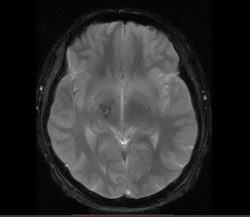

М, 27 лет. Жалобы на головные боли. ЧМТ в анамнезе. Стационар выставил внутримозговую гематому по КТ, полечили, отпустили.  К нам пришел на контроль.

Локализация таламус, граница коркового/мозгового, похоже на множественные кавернозные ангиомы. То, что в левой лобной?

Хочу посоветоваться с коллегами).  Дифференциальный ряд построить. Например токсоплазмоз, метастазы....в общем жду.

Сложно представить у молодого человека и каверномы, и метастазы одновременно.

Наверное, все же множественные каверномы, слева -осложненная кровоизлиянием.

Пришел к выводу, что сдесь все таки не каврномы, а мелкоочаговые кровоизлияния (ДАП). Учитывая травму и пребывание после этого  пациента в коме.